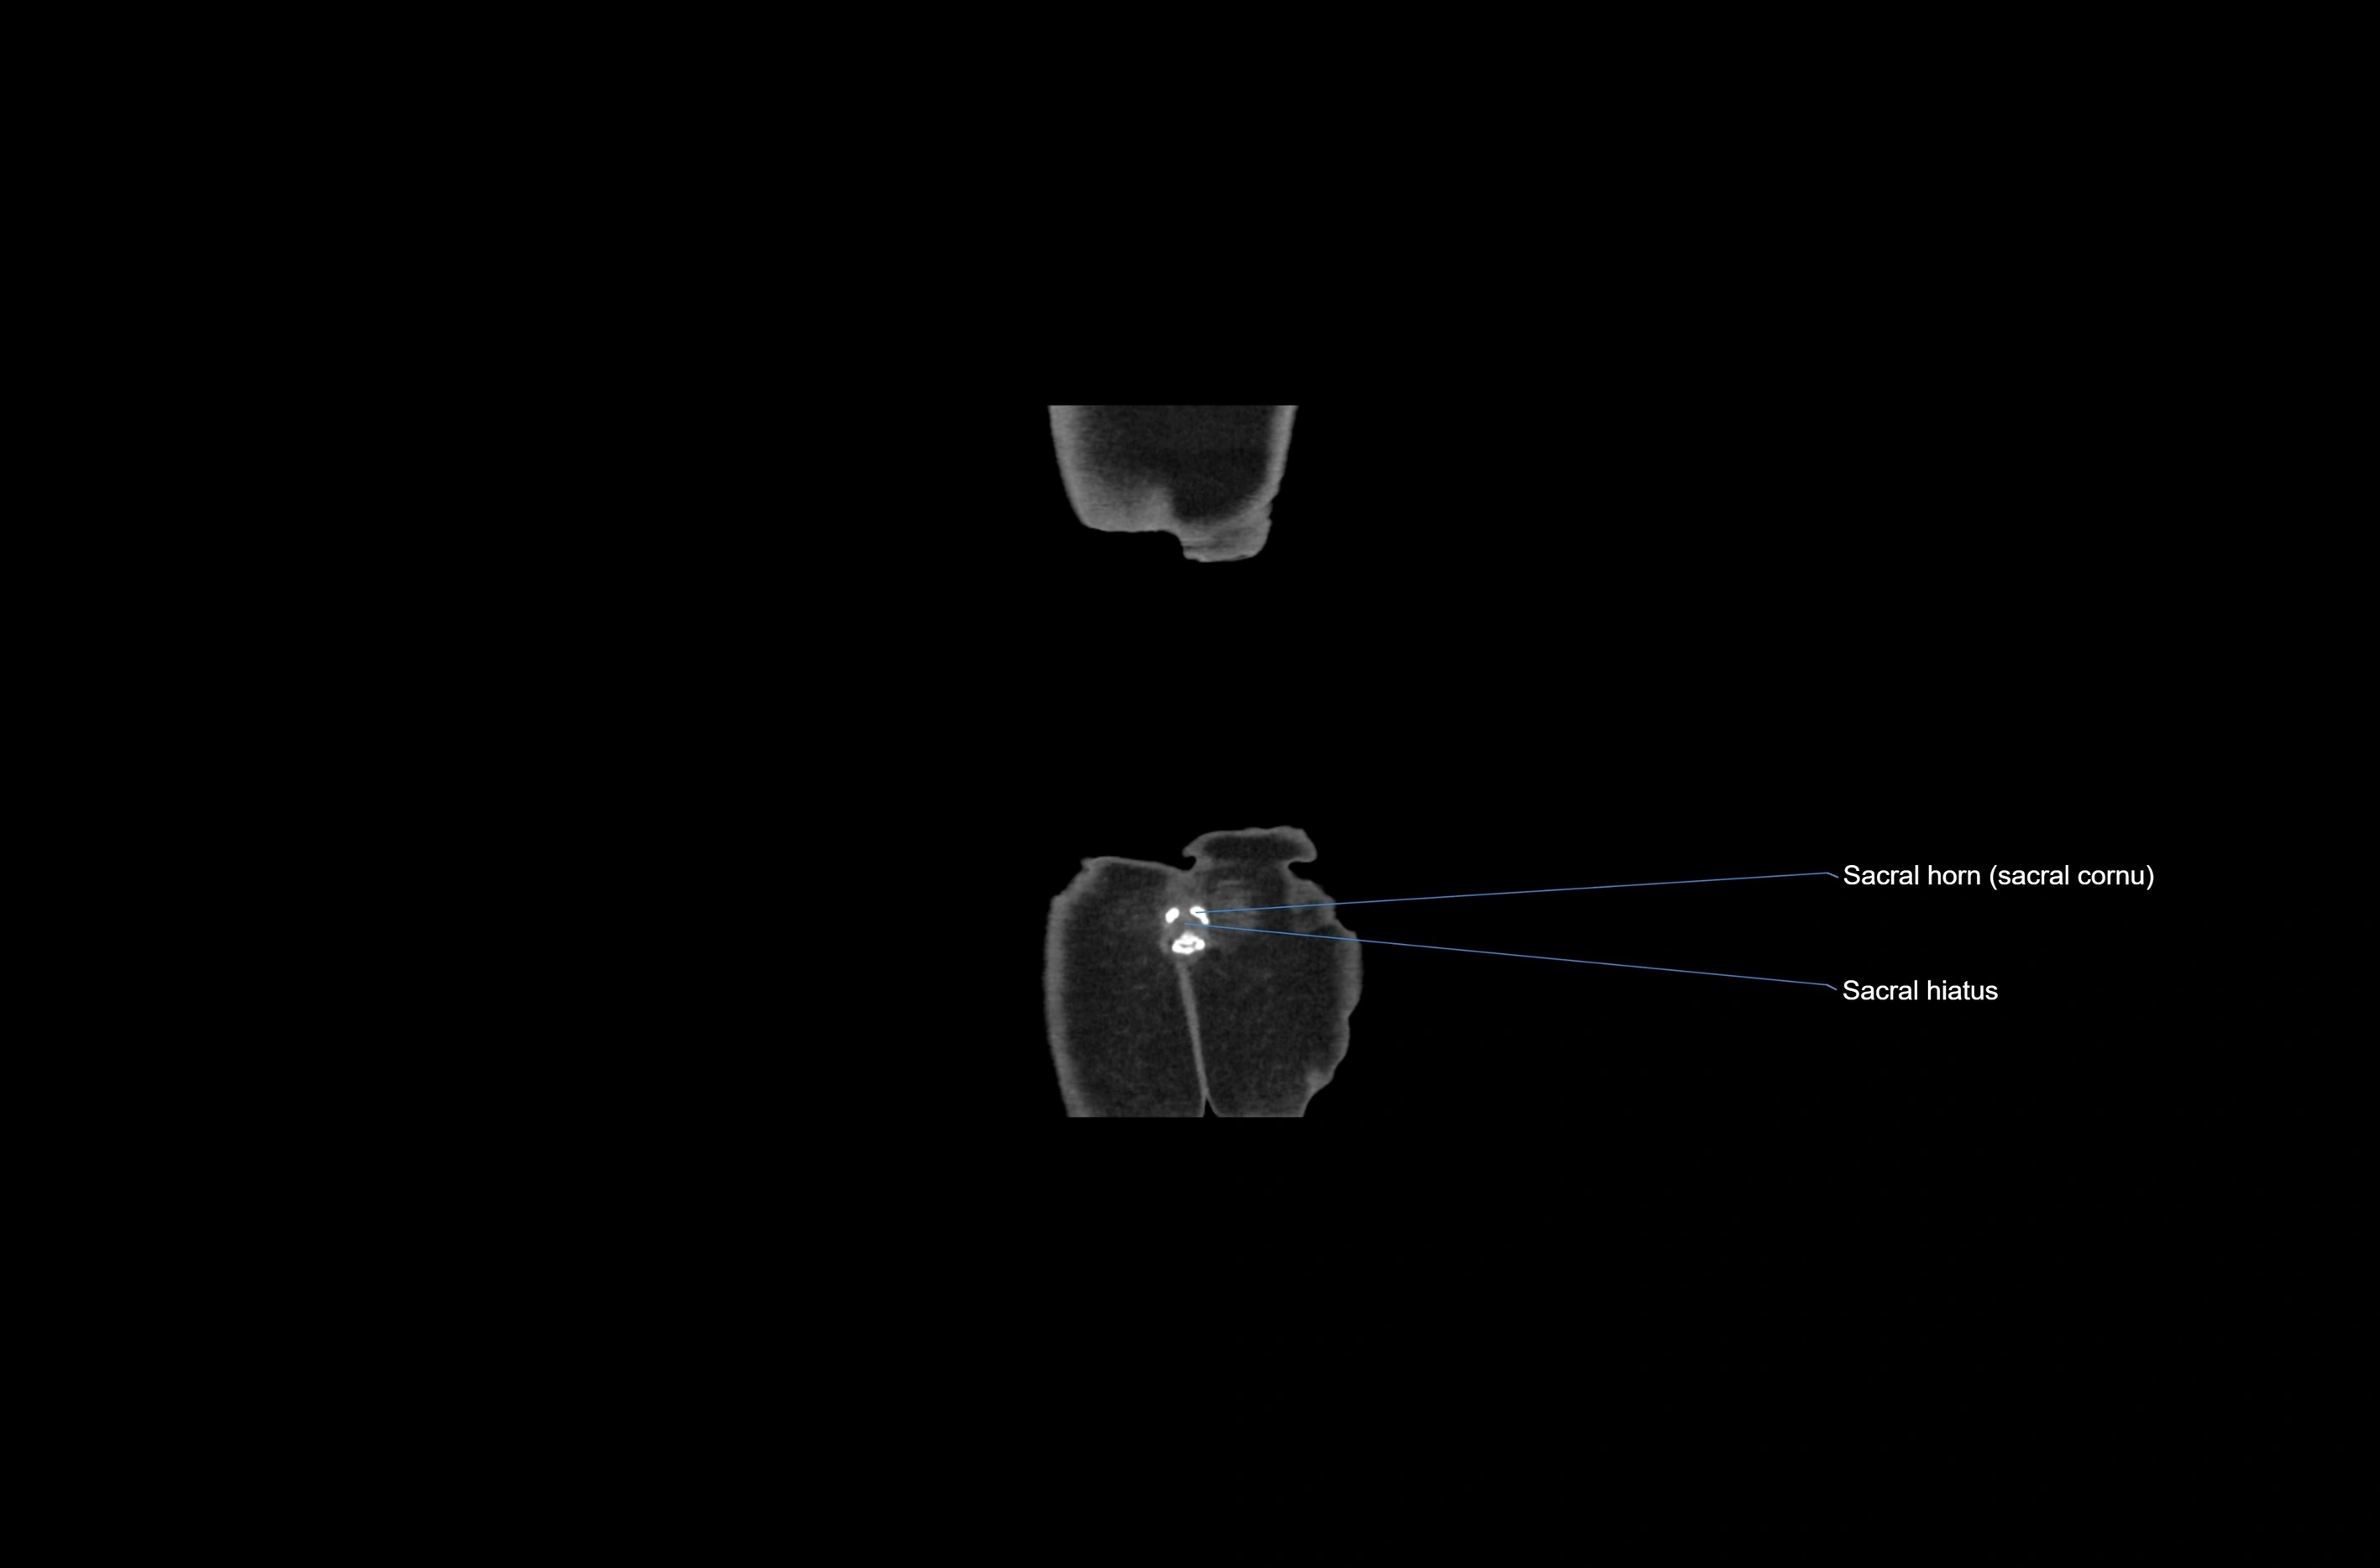

- Sacral cornu (sacral horn)

- Sacral hiatus